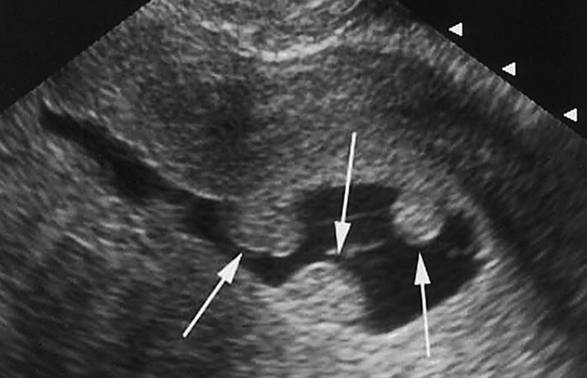

Для диагностики новообразований врач проведет гинекологическое обследование с пальпацией матки и назначит УЗИ. Полип в матке на УЗИ выглядит как более толстый овальный или круглый нарост на ножке. Во время исследования врач обращает внимание на расширение полости матки и местное утолщение эндометрия.

Ультразвуковое исследование — самый доступный и высокоинформативный метод выявления новообразований в матке. На основании полученных результатов гинеколог составляет описание полипа в матке на УЗИ. Полип в матке — это новообразование, растущее из эндометрия.

Полип имеет простую структуру, он образован телом и ножкой, которая прикрепляет образование к стенке матки. На фото полипа матки на УЗИ, при данной патологии прослеживаются признаки эха в изменении полости матки, овальной или круглой формы новообразования, его однородности.